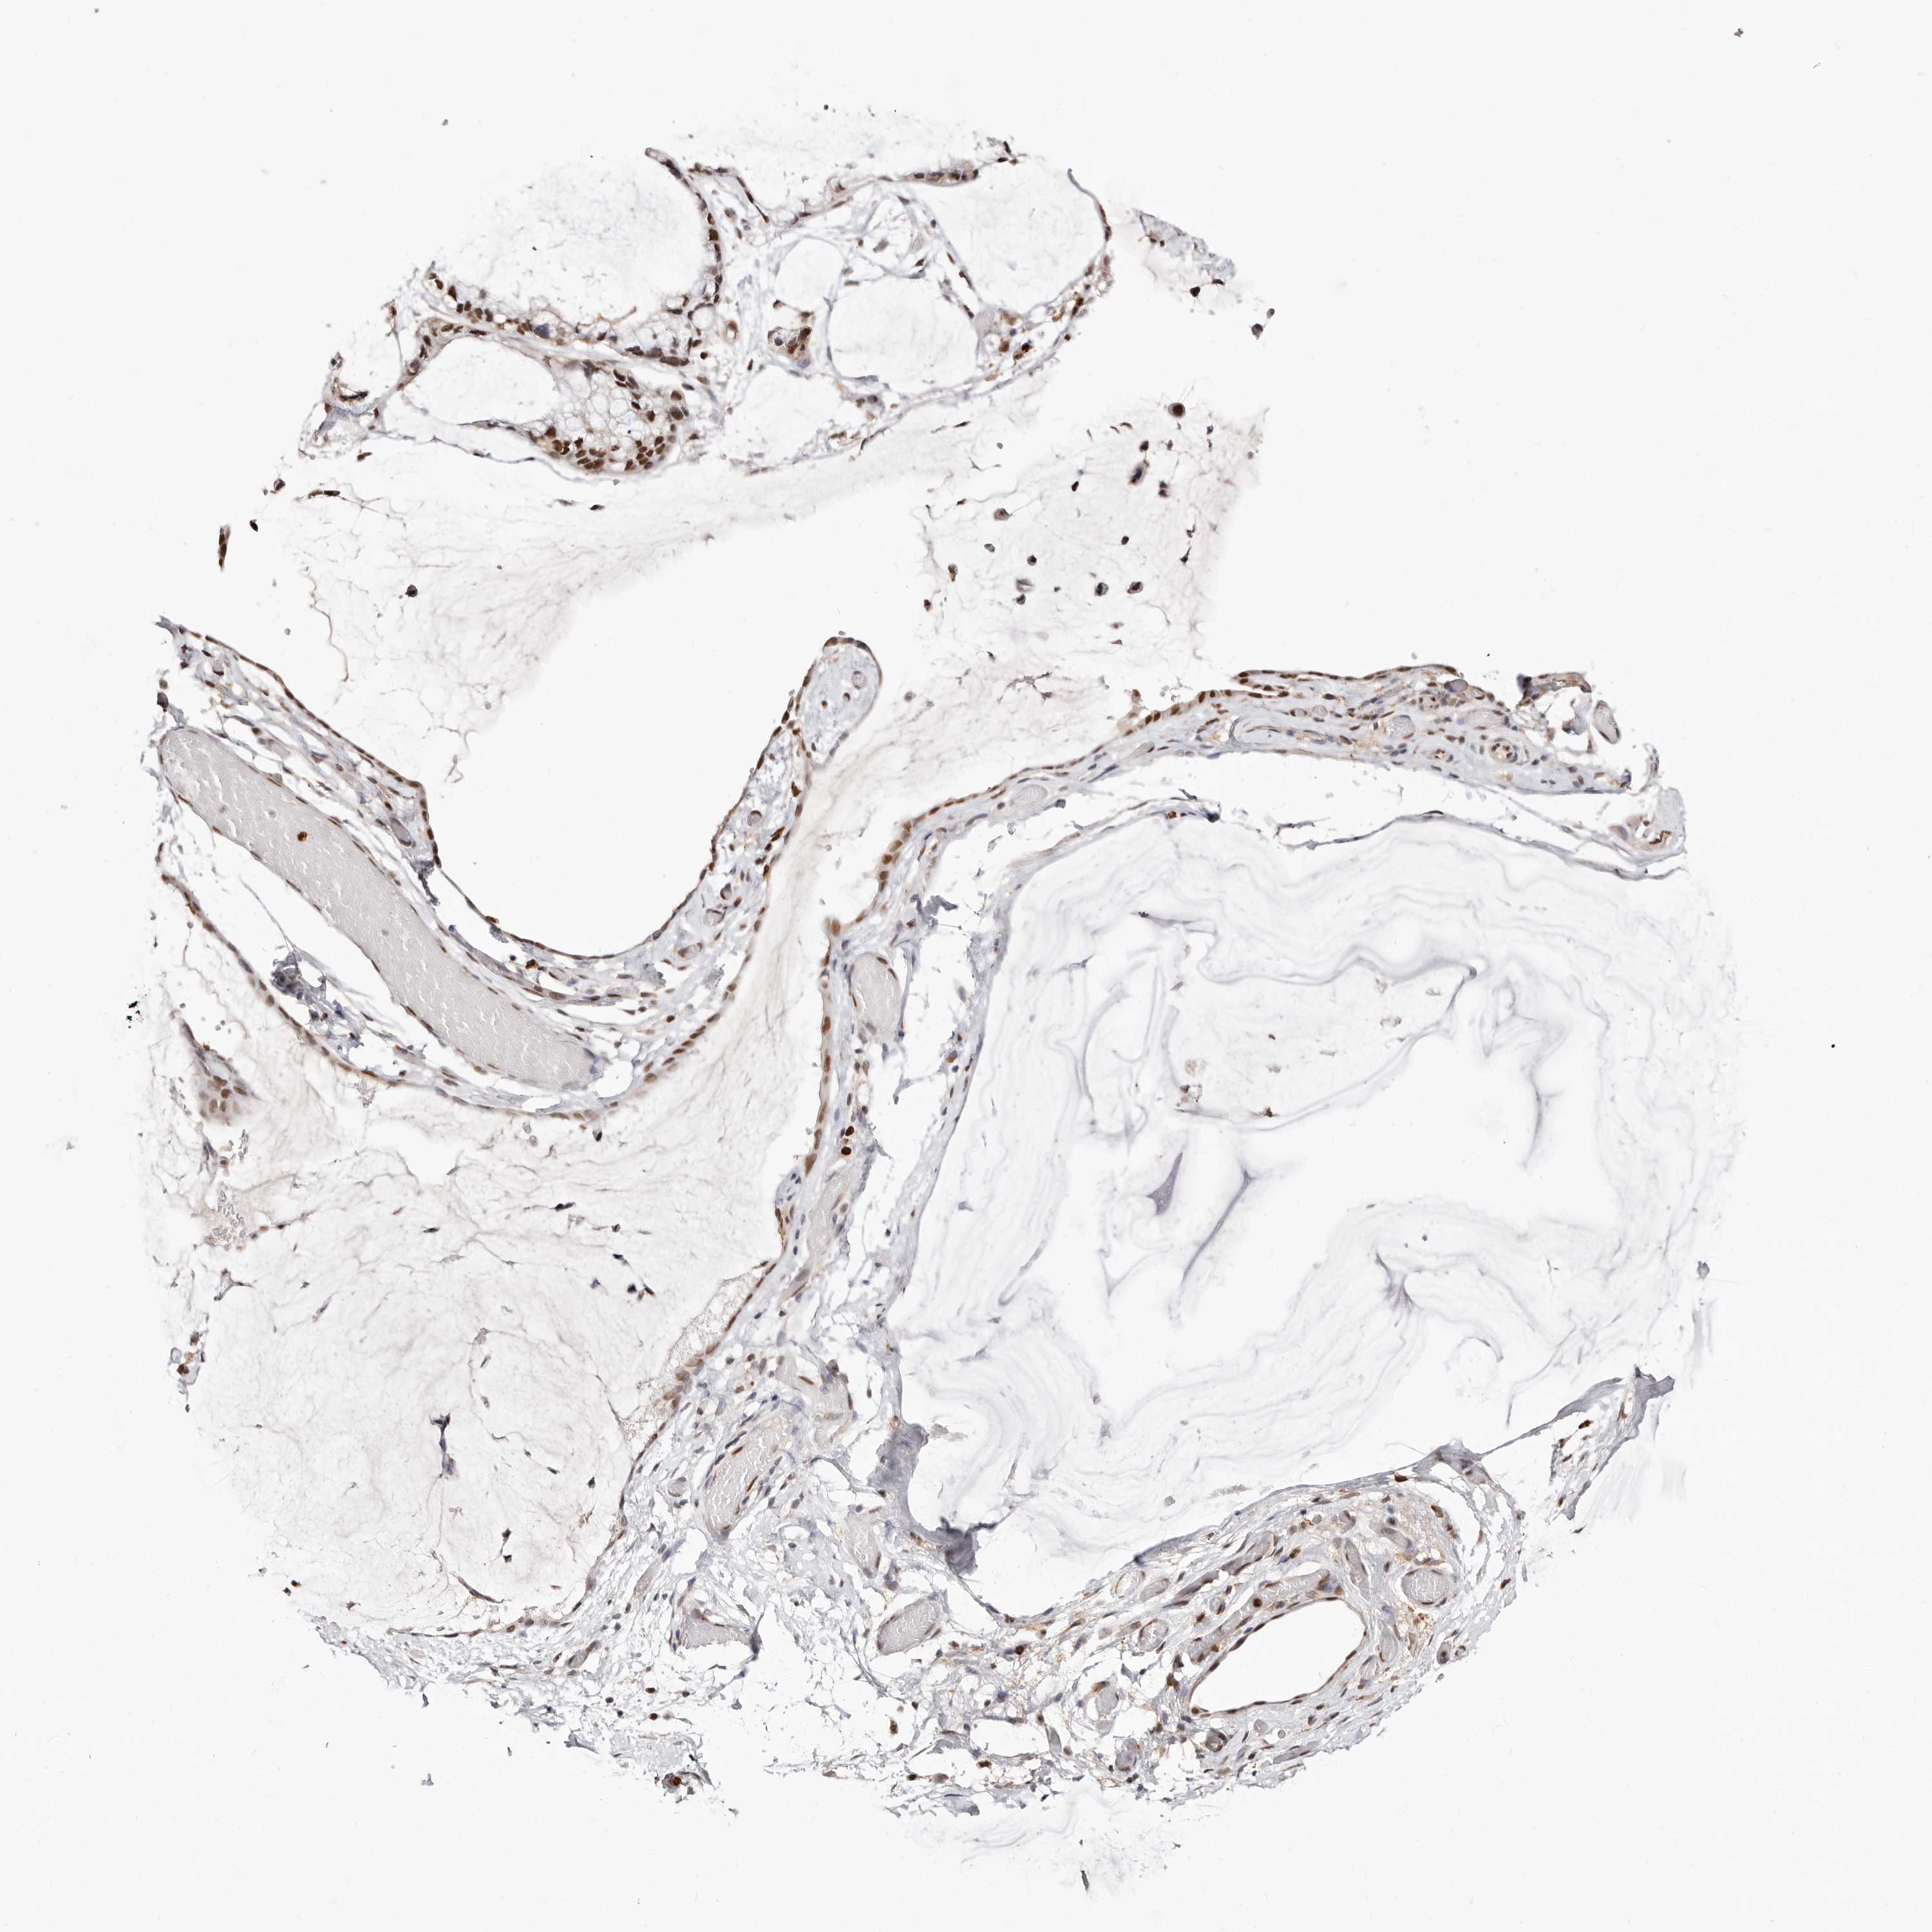

OVARIAN CANCER - Protein expressioni

A mouse-over function shows sample information and annotation data. Click on an image to view it in a full screen mode. Samples can be filtered based on level of antibody staining by selecting one or several of the following categories: high, medium, low and not detected. The assay and annotation is described here.

Note that samples used for immunohistochemistry by the Human Protein Atlas do not correspond to samples in the TCGA dataset.

Antibody stainingi

Antibody staining in the annotated cell types in the current human tissue is reported as not detected, low, medium, or high, based on conventional immunohistochemistry profiling in selected tissues. This score is based on the combination of the staining intensity and fraction of stained cells.

Each image is clickable and will lead to virtual microscopy that enables deeper exploration of all samples and also displays staining intensity scores, fraction scores and subcellular localization as well as patient and tissue information for each sample.

Antibody HPA029480

Antibody HPA029481

Cystadenocarcinoma, serous, NOS

Carcinoma, endometroid

Cystadenocarcinoma, mucinous, NOS

Carcinoma, NOS